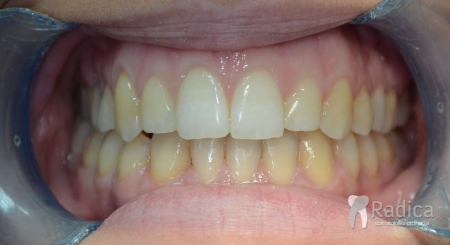

U galeriji slika su prikazani klinički slučajevi ovakvih odraslih pacijenta bilo da se radi samo o ortodontskoj terapiji ili predprotetskoj ortodonciji.